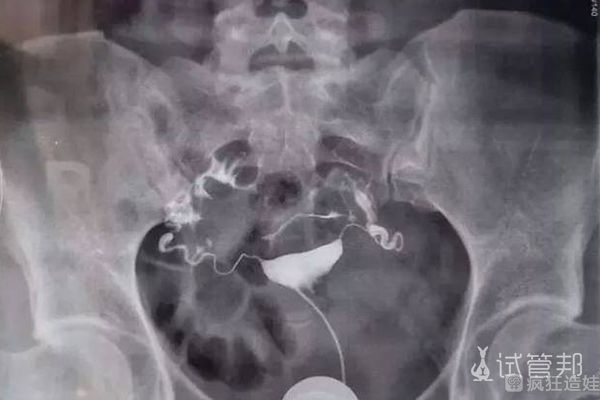

第十三天:胚胎移植当天。医生通知我,一个卵子受精成功,第三天分裂成8个细胞。医生说最好尽快把这个受精卵放入母体,因为这样对它的发育环境会更好。胚胎移植手术不需要麻醉,过程就像妇科检查一样,很快就完成了。然后我在病房躺了两个小时。与此同时,护士会进来给我量血压,并给我打一针抗流产针。胚胎培养和胚胎移植的费用大概在20000元左右。